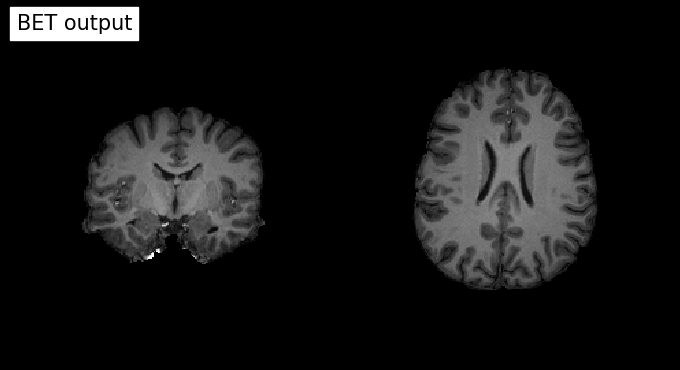

# Plot original input file

plotting.plot_anat(input_file, title='BET input', cut_coords=(10,10,10),

display_mode='ortho', dim=-1, draw_cross=False, annotate=False);

# Plot skullstripped output file (out_file) through the outputs property

plotting.plot_anat(res.outputs.out_file, title='BET output', cut_coords=(10,10,10),